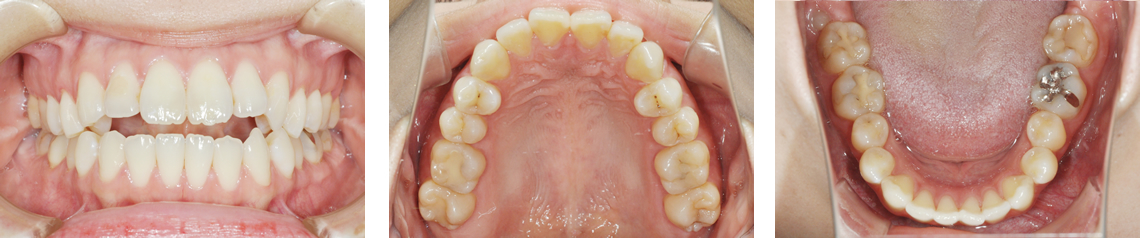

| 年齢 | 23歳3か月 |

|---|---|

| 主訴 | 歯のでこぼこが気になる |

| 診断名 | 叢生 |

| 治療に用いた主な装置 | マルチブラケット装置 顎間ゴム |

| 抜歯部位 | 上下顎両側第一小臼歯 |

| 動的治療期間 | 2年10か月 |

| 治療費用 | 89万円+消費税 |

| リスクと副作用 | 口腔内が清掃不良の場合、虫歯や歯周病のリスクが高くなります。 動的治療中は痛みが出る可能性があります。 歯肉退縮、歯根吸収が生じる可能性があります。 |